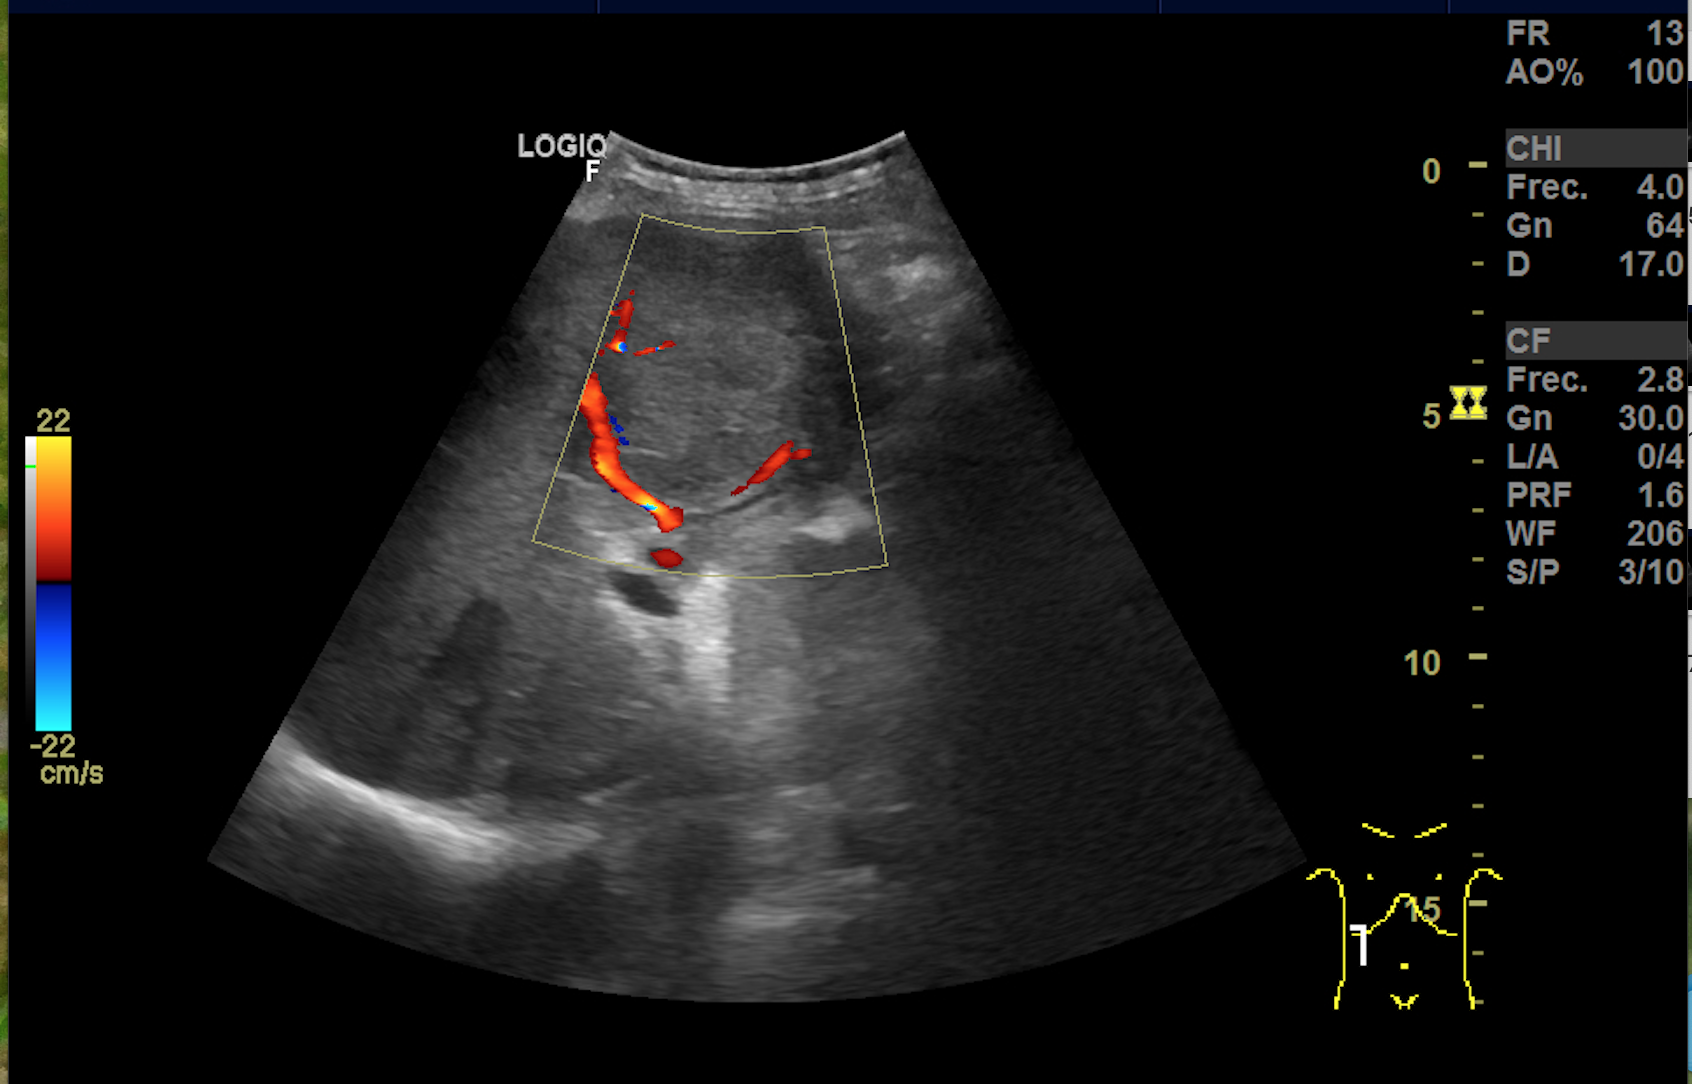

Hallazgos ecográficos

Hígado aumentado de tamaño donde se observan, ocupando gran parte del lóbulo hepático derecho al menos 2 imágenes redondeadas heteroecoicas vascularizadas de hasta 11 cm de diámetro. Vesicula bien replecionada con imagenes heteroecoicas con sombra posterior en su interior. El hemiabdomen izquierdo esta ocupado por lesiones anecoicas que impresionan de quistes renales. No observamos líquido libre.